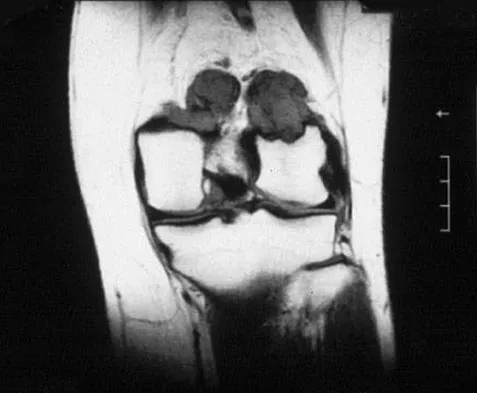

A 31-year-old woman has increasing pain and tightness in her right knee, with occasional stiffness and recurrent hemorrhagic effusions. MRI scans are shown in Figures 2a and 2b. What is the most likely diagnosis?

PVNS is a rare inflammatory granulomatous condition of unknown etiology, and causes proliferation of the synovium of joints, tendon sheaths, or bursa. The disorder occurs most commonly in the third and fourth decades but can occur at any age. MRI provides excellent delineation of the synovial disease. Characteristic features of PVNS on MRI include the presence of intra-articular nodular masses of low signal intensity on T1- and T2-weighted images and proton density-weighted images. Synovial biopsy should be performed if there is any doubt of the diagnosis. Total synovectomy (open or arthroscopic) is required for the diffuse form, although recurrence is common. Rheumatoid arthritis and synovial chondromatosis are not typically associated with hemorrhagic effusions. De Ponti A, Sansone V, Malchere M: Result of arthroscopic treatment of pigmented villonodular synovitis of the knee. Arthroscopy 2003;19:602-607. Chin KR, Barr SJ, Winalski C, et al: Treatment of advanced primary and recurrent diffuse pigmented villonodular synovitis of the knee. J Bone Joint Surg Am 2002;84:2192-2202.